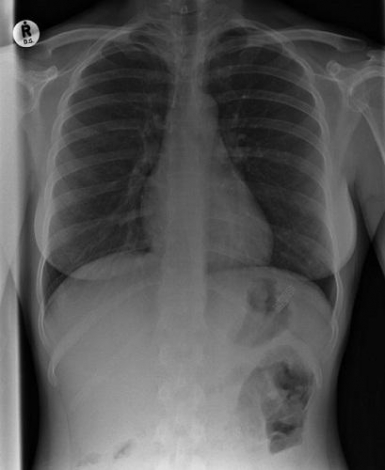

12879410891175362647.jpg

這張X照片展現了嵌入一位患者胸部的子彈。